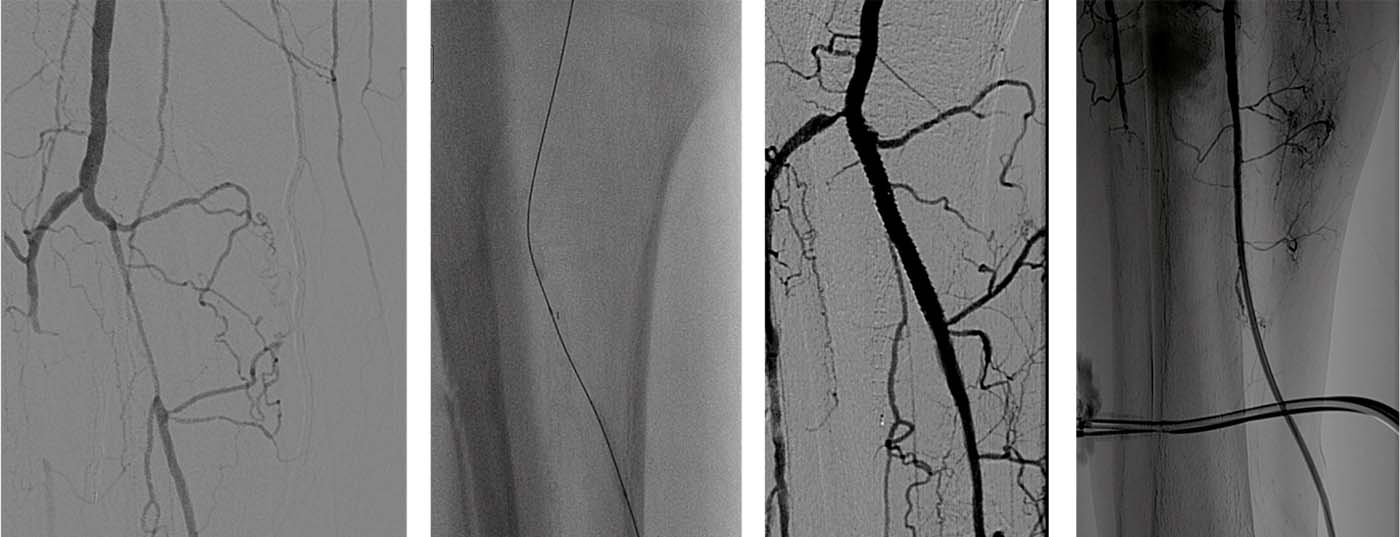

Die Katheter-gestützte Therapie von Gefässerkrankungen hat sich in den letzten Jahren deutlich verändert. Rapider techni­scher Fortschritt und grössere klinische Erfahrungen ermöglichen heute die Rekanalisation auch stark verkalkter und langstreckiger arterieller Verschlüsse. Eine Reihe von Kathetern ermöglicht die aktive Beseitigung von thrombotischen und ­embolischen Pathologien, so dass komplexe, vor einigen ­Jahren technisch noch nicht durchführbare Eingriffe heute ­sicher vorgenommen werden können.